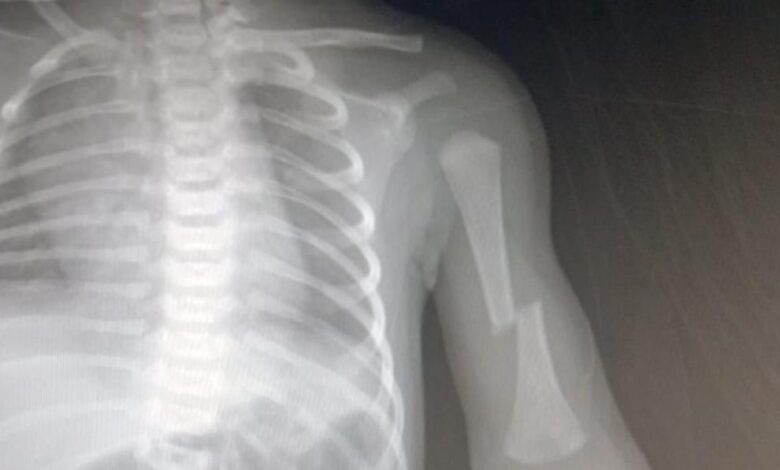

प्रसव के दौरान नवजात के हाथ व गले की हड्डी टुटी, स्वास्थ्य केंद्र पर लापरवाही का आरोप

जिसमें पहले शिशु के प्रसव के दौरान सीएचसी में एएनएम की लापरवाही से नवजात के गर्दन की हड्डी एवं हाथ ही हड्डी तीन जगह से टूट गई है. सविता की तकलीफ बढ़ने के बाद आनन फानन में उसे दूसरे अस्पताल रेफर कर दिया गया. जिसके बाद परिजन उसे लेकर चंदवा के एक निजी अस्पताल पहुंचे. वहां दूसरे बच्चे का जन्म ऑपरेशन से हुआ. प्रसूता ने जिला प्रशासन से दोषी स्वास्थ्यकर्मियों के विरुद्ध कार्रवाई करने की गुहार भी लगाया है. दूसरी ओर मामले में सीएचसी प्रबंधन मामले में पल्ला झाड़ती नजर आ रही है. इन घटनाओं से स्थानीय लोगों में काफी रोष है.बता दें कि पिछले सप्ताह इसी केंद्र की एएनएम पर लापरवाही का आरोप लगा था, जिसमें एक प्रसूता की मौत प्रसव के दौरान हो गयी थी.